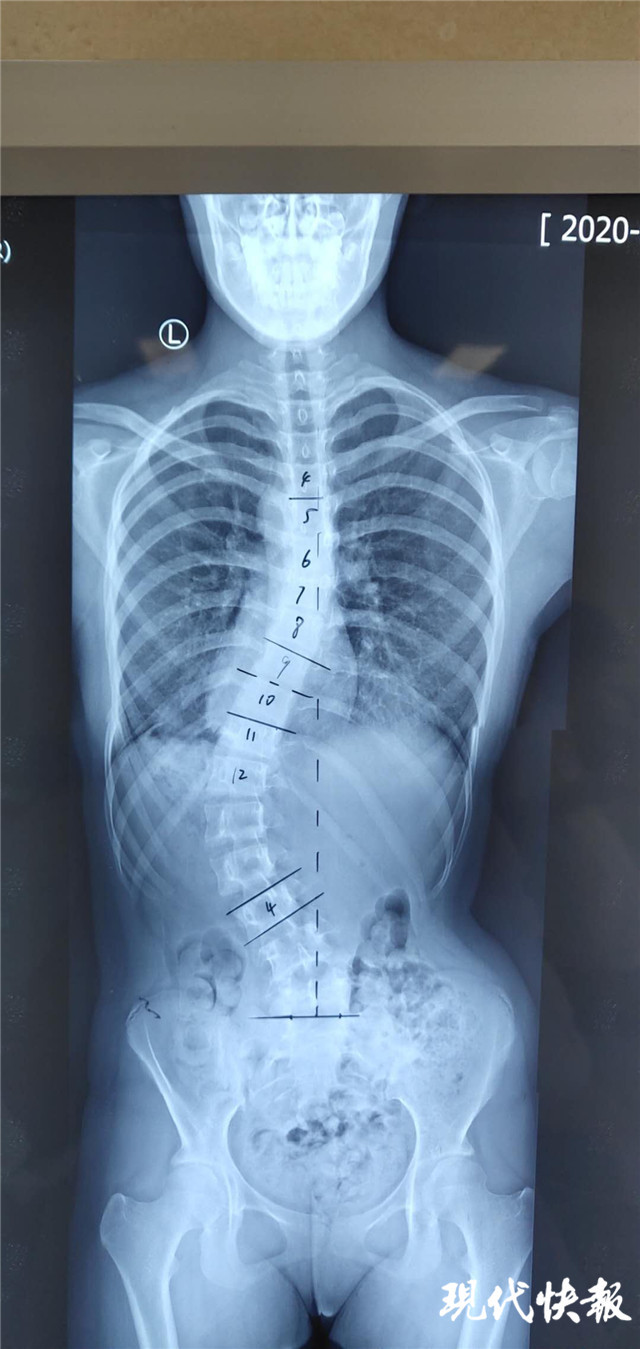

先天性脊柱侧凸站立位全脊柱正侧位:胸椎右侧弯,cobb角53°(t2-t7),t3